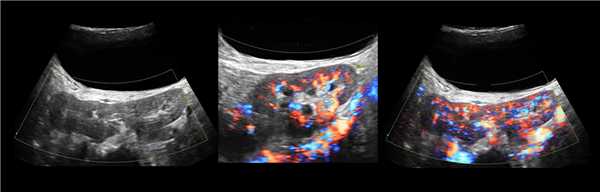

а) Эхограммы.

б) Серия компьютерных томограмм.

У 2 (1,2%) больных отмечена увеличенная "губа" над воротами почки (рис. 3а-в).

а) Эхограмма.

б) Экскреторная урограмма.

в) КТ с контрастным усилением.

Наиболее частой причиной псевдоопухоли была "гипертрофия" столбов Бертена или "перемычки" паренхимы почек - у 153 (86,4%) пациентов (рис. 3 г-е). "Перемычки" паренхимы были отмечены не только при различных удвоениях чашечно-лоханочных систем почек, но и при различных их сращениях и незавершенных поворотах почек.

Рис. 3 (г-е). Псевдоопухоль гипертрофия Бертена (неполная "перемычка" паренхимы) в среднем отделе правой почки.

г) Эхограмма.

д) Экскреторная урограмма.

е) КТ с контрастным усилением.

Бывает колонна Бертини врезается в центральную часть почки, разделяя ее полно или неполно на две части. Такая паренхиматозная перемычка — это паренхима полюса одной из эмбриональных долек, которые сливаясь образуют почку; состоит из коры, пирамид, колонн Бертини — все элементы без признаков гипертрофии или дисплазии. Термин гипертрофия колонны Бертини не отражает морфологию структуры, точнее считать данное образование паренхиматозной перемычкой.

Рисунок. На УЗИ округлое образование разделяет почечный синус на два сегмента с общей лоханкой; междолевые артерии огибают образование; эхогенность и интенсивность сосудистого рисунка внутри близка корковой зоне. Заключение: Гипертрофия колонны Бертини или неполная паренхиматозная перемычка. Это вариант нормального строения почки. Термин «неполное удвоение ЧЛК» неверный, т.к. неполная паренхиматозная перемычка не является признаком удвоения ЧЛК.

Рисунок. На УЗИ синус почки разделяет полная паренхиматозная перемычка (1, 2). В таких случаях разграничить удвоение почки от гипертрофии колонны Бертини поможет экскреторная урография. Удвоенная почка покрыта общей фиброзной капсулой. Полное удвоение предполагает наличие двух лоханок, двух мочеточников и двух сосудистых пучков. Неполноудвоенная почка (3) питается одним сосудистым пучком, мочеточник может быть удвоен вверху и впадать в мочевой пузырь одним или двумя устьями. Удвоение ЧЛК и мочеточников — фактор риска развития патологии (пиелонефрита, гидронефроза и др.).

Рисунок. На УЗИ синус почек широкий, неоднородной эхоструктуры (1, 2). На фоне гиперэхогенного жира гипоэхогенный очаг округлой формы (2), при ЦДК междолевые сосуды проходят через гипоэхогенную зону без смещения (3) — это гипоэхогенный жир. При ожирении липоматоз синуса можно ошибочно принять за атрофию паренхимы.